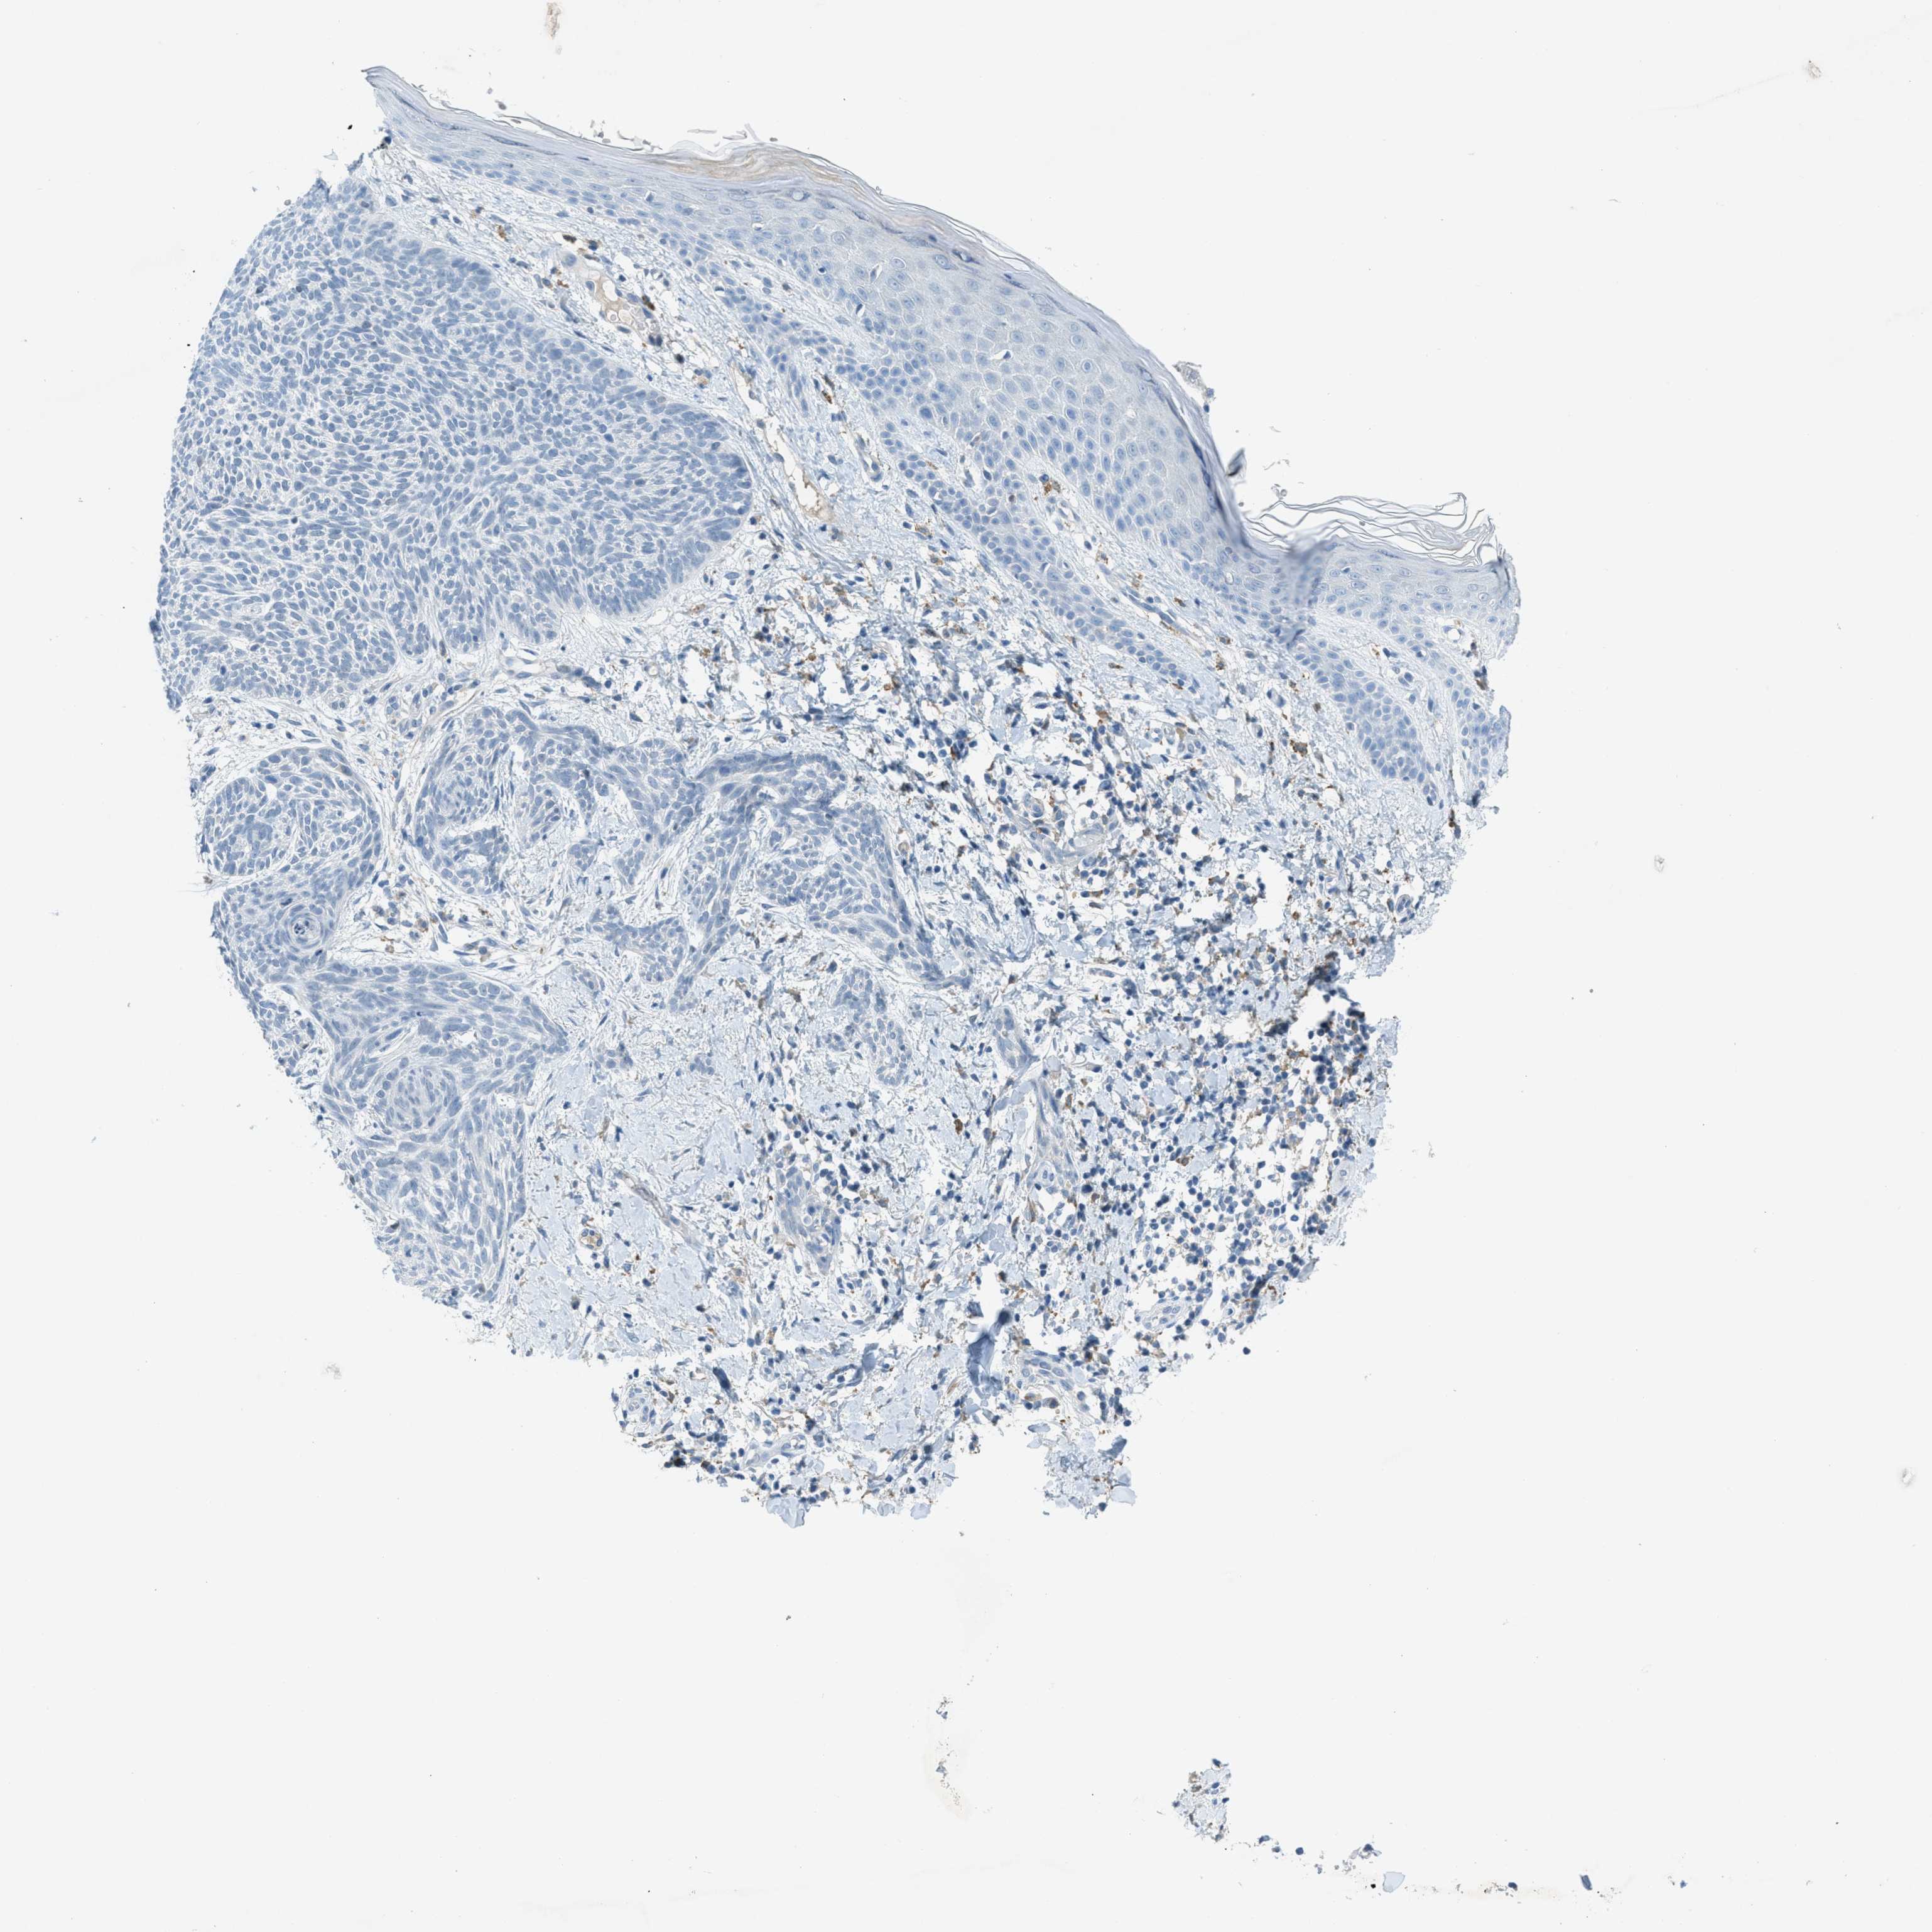

SKIN CANCER - Protein expressioni

A mouse-over function shows sample information and annotation data. Click on an image to view it in a full screen mode. Samples can be filtered based on level of antibody staining by selecting one or several of the following categories: high, medium, low and not detected. The assay and annotation is described here.

Each image is clickable and will lead to virtual microscopy that enables deeper exploration of all samples and also displays staining intensity scores, fraction scores and subcellular localization as well as patient and tissue information for each sample.

Antibody HPA013856

Basal cell carcinoma

Squamous cell carcinoma in situ, NOS